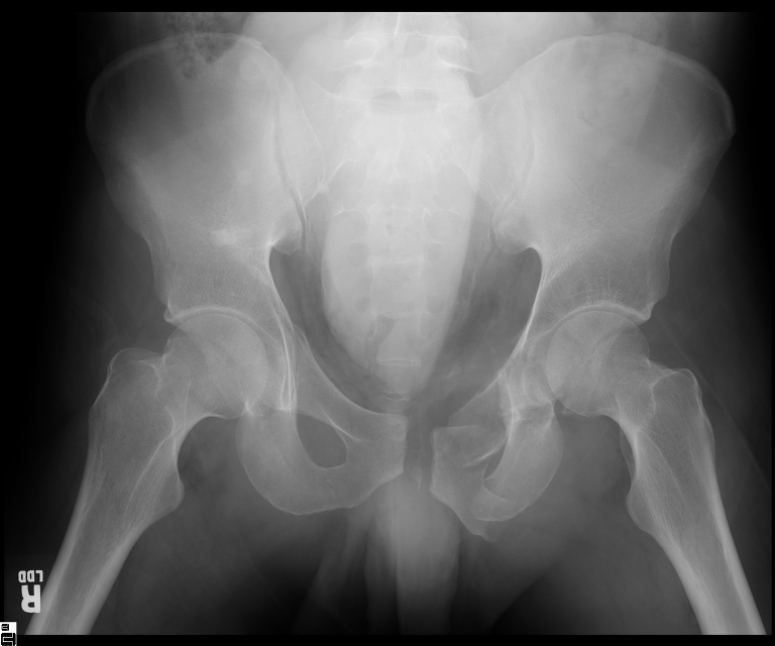

25 yo brittle diabetic, became hypoglycemic and passed out on his motorcycle. Sustained bilateral lateral Hoffa fractures with associated LCL injury on the right and right distal radius fracture. I have questions regarding his pelvic ring/acetabular fracture on the left. Appears to be a very low posterior column fracture with associated posterior wall, marginal impaction. Superior and inferior rami fractures as well on the left giving him a floating segment of inf ramus/ischium/posterior column, but no detectable posterior ring injury. Should the posterior column/posterior wall fracture be addressed surgically because of the marginal impaction? Or is this fracture low enough to be treated non-operatively? I appreciate the input.

I believe the more serious component of the acetabular fracture to be the large (almost 50%) impacted, comminuted zone of the posterior wall. In several series, including the one I reported at the AAOS in 2002 in Dallas of 100 acetabular fractures with posterior wall involvement, all repaired by a single surgeon (Kyle Dickson), those with posterior wall impaction did significantly worse than those without. Nevertheless, the large area of involvement, as well as a joint designed for very low tolerances of "out of round", would indicate that the best chance for avoiding early degenerative changes would be an anatomic repair.

It's an interesting case. The plain films show the impaction, but most of the joint looks pretty good. The CT cuts look awful, though.

The impaction is so big I don't think I would ignore it. It IS down low, but it takes up almost the whole southern hemisphere of his joint.